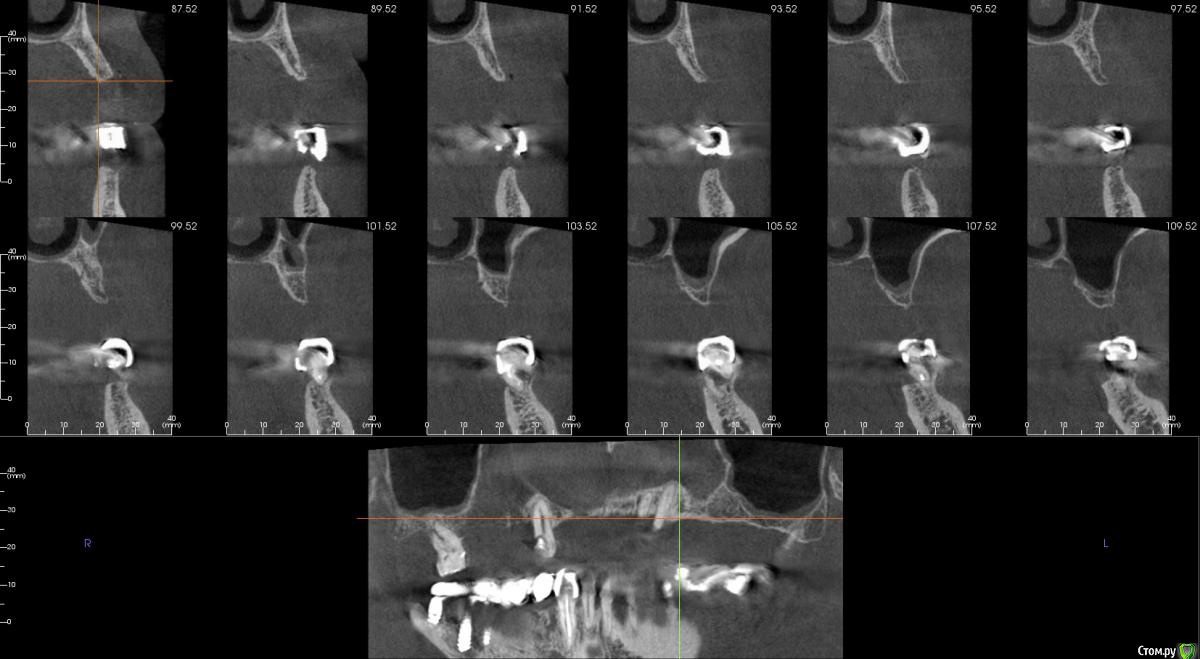

kamranchick Опубликовано 20 сентября, 2016 Поделиться Опубликовано 20 сентября, 2016 Интересует сторона 2. там хочу сделать соссидж, через несколько месяцев сделать закрытый синус и установить 2 винта в области 14 и 16, как вы думаете?и можно ли сделать конструкцию не брав во внимание фронтальный отдел? пациент финансово не тянет фронт Ссылка на комментарий

kamranchick Опубликовано 22 февраля, 2017 Автор Поделиться Опубликовано 22 февраля, 2017 Интересно что в итоге получилось, какой метод выбрали?во фронте блоки в области 2 сегмента сосидж Ссылка на комментарий